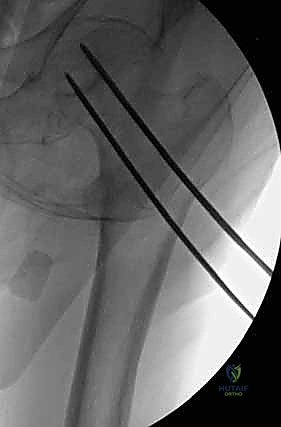

هي مسامير طبية متطورة مصنوعة من التيتانيوم (Titanium) أو الفولاذ المقاوم للصدأ (Stainless Steel). السمة المميزة لها هي وجود "تجويف" أو نفق يمتد عبر مركز المسمار بالكامل. هذا التصميم العبقري يسمح للجراح بإدخال سلك توجيهي رفيع (Guide Wire) أولاً في العظم لتحديد المسار الدقيق، ثم يتم تمرير المسمار المجوف فوق هذا السلك لينزلق مباشرة إلى المكان المحدد بدقة مليمترية.

لماذا نستخدم 3 مسامير؟ (هندسة المثلث المقلوب)

يعتمد الأستاذ الدكتور محمد هطيف على مبادئ الميكانيكا الحيوية (Biomechanics) في التثبيت. يتم عادةً إدخال ثلاثة مسامير متوازية في عنق الفخذ. لا يتم وضعها بشكل عشوائي، بل تُرتب في شكل مثلث مقلوب (Inverted Triangle):

1. المسمار السفلي (Inferior Screw): يُوضع أولاً ليكون الدعامة الأساسية التي تستند على الكورتيكس السفلي الصلب لعنق الفخذ (Calcar)، وهو يتحمل أكبر قدر من وزن الجسم.

2. المسمار الأمامي العلوي (Antero-superior Screw).

3. المسمار الخلفي العلوي (Postero-superior Screw).

هذا التوزيع الثلاثي يوفر ثباتًا دورانيًا (Rotational Stability) ممتازًا ويمنع رأس الفخذ من الانزلاق أو الدوران حول محوره، كما يسمح بانضغاط الكسر (Compression) على طول خط الكسر، مما يحفز الخلايا العظمية على الالتئام السريع.